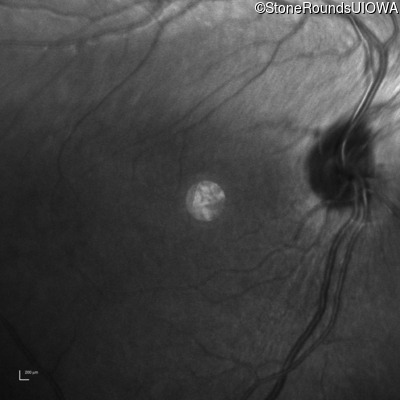

Infrared Fundus Photograph - Right - 10/125 -1

Exemplar

Infrared Fundus Photograph - Left - 10/100 -1